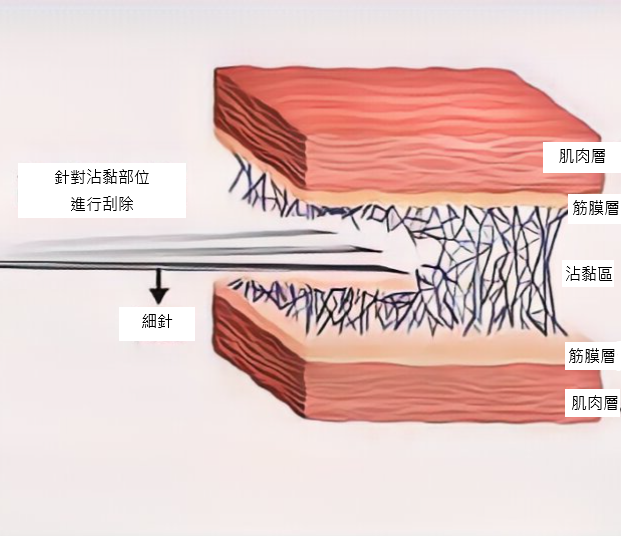

2.不破壞正常組織下,針對沾黏部位解離

細微針刮除沾黏部位 – 針對局部纖維化區域進行刮除(幾乎無痛)